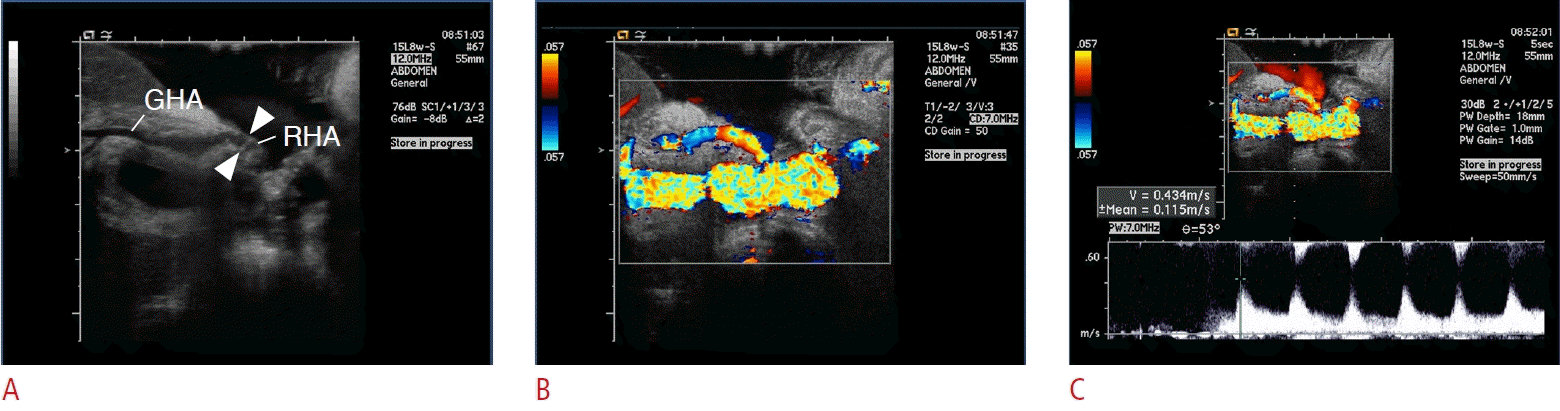

Fig. 2.

Hepatic artery stenosis on intraoperative ultrasonograms.

A. Grayscale intraoperative sonogram shows mild waisting and angulation around the anastomosis (dashed circle). B. Color Doppler ultrasonogram shows weak flow of the graft hepatic artery, marked as dark blue color (arrows). C. Spectral Doppler ultrasonogram shows tardus parvus waveform of graft hepatic artery, with decrease of resistive index (<0.5) and prolonged systolic acceleration time (>0.08 seconds). D. Following the revision of the anastomosis, spectral Doppler ultrasonogram shows restored normal waveform of graft hepatic artery.

To detect HA stenosis, the diameter of HA anastomosis is first measured, followed by color and spectral Doppler US of the graft HA to identify abnormal Doppler parameters indicative of HA insufficiency, as follows: peak systolic velocity <30 cm/s, resistive index <0.5, and systolic acceleration time >0.08 seconds [3] (Fig. 2).